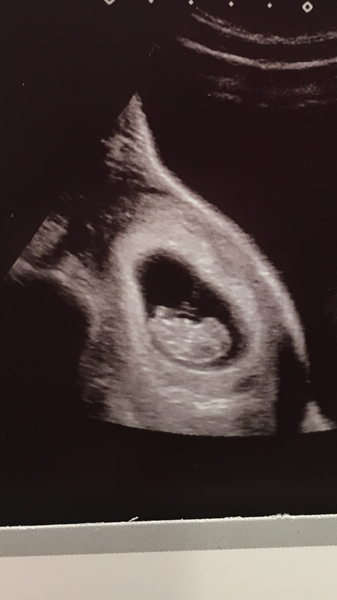

Had our first scan today at 9+1 so still due 16th June. Was an amazing moment but also still doesn’t feel real! They said everything is looking good so feeling very positive now! Just can’t wait for the nausea to calm down abit haha! Hope your all well today !

Great pic @emily1511! I’ve got my scan on Saturday Grin hope to get something that clear!

That's lovely @emily1511 - I'll have my official dating scan on Monday (even though I know from an early scan I'll only be 10+5 then), I'm hoping for a such a nice and clear picture as well :)